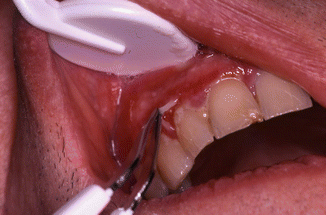

Fig. 35.1

Blisters surrounded by erythema on the gingiva and area of normal mucous membrane